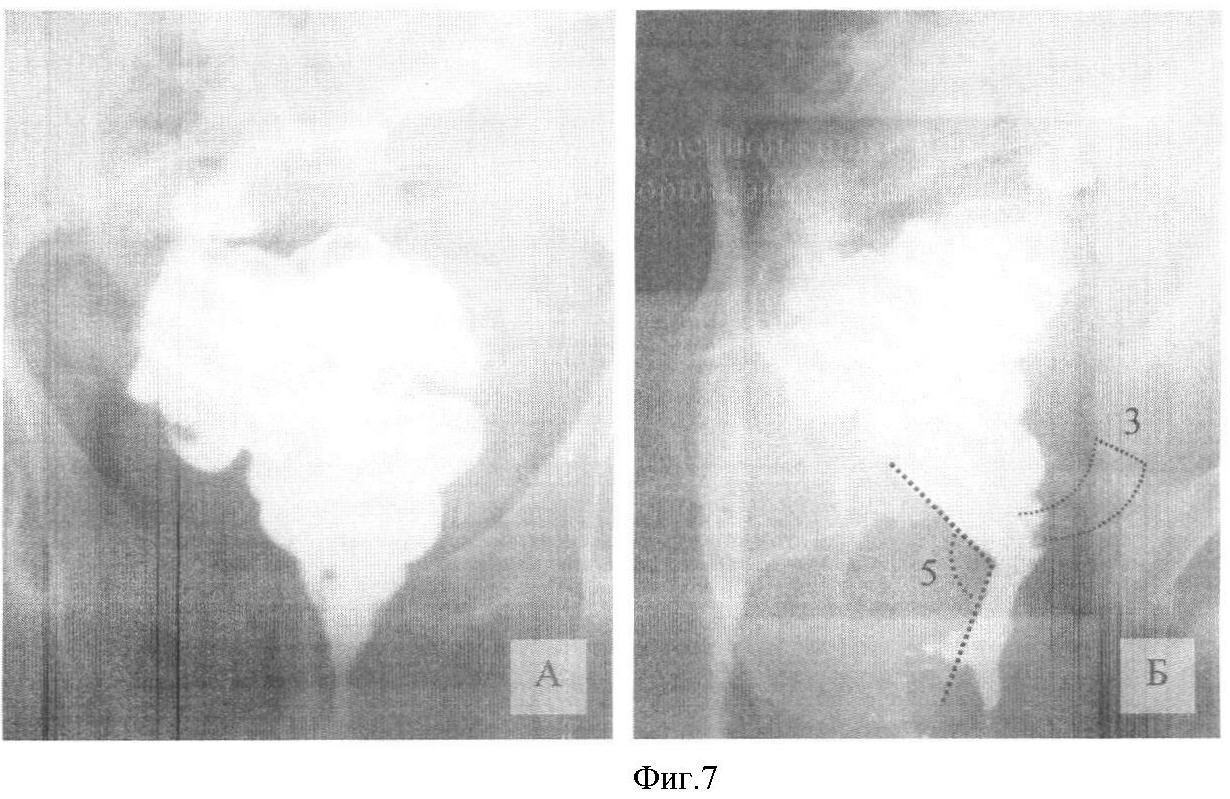

Колоноскопия с хромоскопией (22.08.07).

Тонус анального сфинктера сохранен. Сразу за сфинктером в 1,5-2 см от анального отверстия определяется край опухоли с преимущественным экзофитным ростом. По окружности опухоль занимает от ½ до , по длиннику до 5-6 см (фиг.1). Для объективизации распространения опухоли за пределы ее макроскопических границ выполнена прямая хромоскопия с метиленовым синим (фиг.2). Используя отличительные особенности рельефа слизистой ампулы кишки и опухоли, произведена биопсия: 1 фл. – 4 фр. с проксимального края опухоли, 2 фл. – 3 фр. из зоны диффузного пропитывания слизистой красителем, 3 фл. – 3 фр., из центральной части опухоли, 4 фл. – 3 фр. из дистального края. Толстая кишка осмотрена до купола слепой кишки. В левой половине ободочной кишки определяется несколько дивертикулов 0,8 см без признаков воспаления. Слизистая дистального отдела отечна, гиперемирована. В сигмовидной кишке полип на широком основании 0,8 см, биопсия 2 фр. Заключение: рак прямой кишки, полип сигмовидной кишки 2 типа, одиночные дивертикулы ободочной кишки.

Фиг.1 – видеоколоноскопия: А – нижний край опухоли на границе нижнеампулярного отдела и анального канала (указан стрелками); Б – распространение опухоли по окружности нижнеампулярного отдела прямой кишки (указано пунктирной линией).